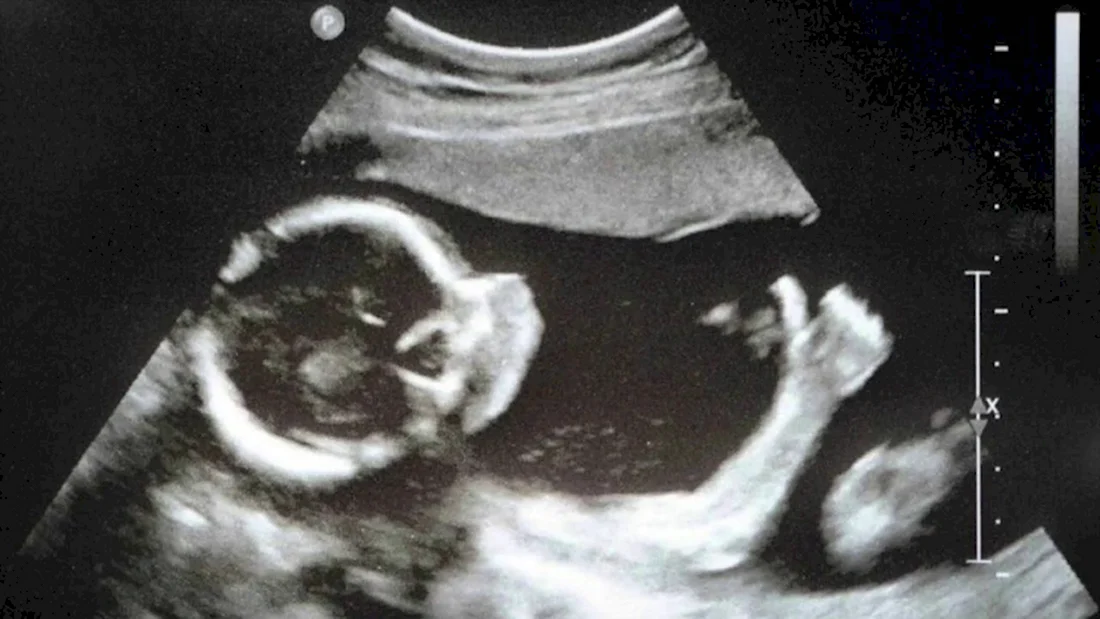

Погрузитесь в волшебный мир развития эмбриона кошки с помощью этой захватывающей галереи фотографий! Вас ждут 39 потрясающих фото и картинок, которые позволят вам увидеть каждый этап развития эмбриона. Эта подборка фотографий сразу привлечет ваше внимание и заставит задуматься о том, насколько удивительным может быть природа. Порадуйте свои глаза этой удивительной коллекцией фотографий и узнайте больше об удивительной жизни эмбрионов кошек!